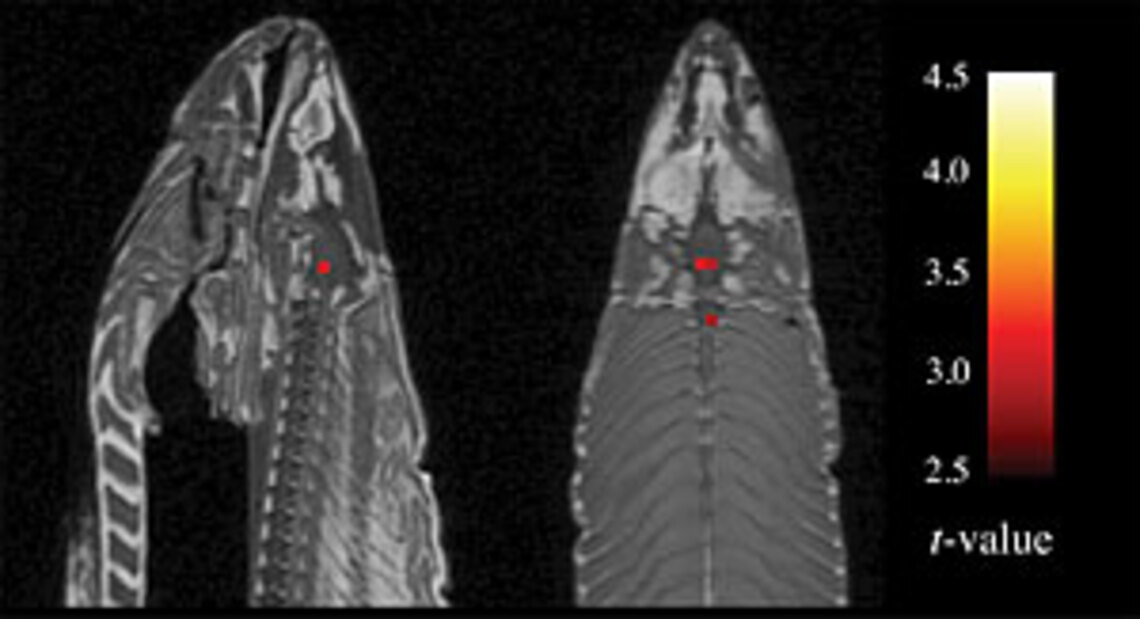

Le problème étant que, soumis à un traitement statistique, certains des voxels (unité de volume sur laquelle la mesure est réalisée) démontraient des variations statistiquement significatives. En somme, la tâche de lecture des émotions humaines activait le cerveau du saumon mort ! Les auteurs prirent un malin plaisir à montrer l'image du cerveau de notre sympathique salmonidé un peu trépassé, s'activant devant le spectacle des embarras, joies et déceptions humaines (le point rouge sur l'image)

Evidemment, il s'agissait d'un artéfact méthodologique, dont les auteurs étaient parfaitement conscients, et qui relevait du problème des comparaisons multiples. Etudiant les variations observées sur environ 130 000 voxels, le traitement statistique pouvait mettre en évidence des différences liées aux variations spontanées du bruit de fond. Plus on multiplie les tests, plus on a de chances de trouver une variation significative. Ainsi, en présentant ce "travail", les auteurs souhaitaient surtout souligner le risque qu'il y a à multiplier les comparaisons statistiques jusqu'à l'obtention d'un résultat significatif, qui peut, nécessairement, être lié au hasard.